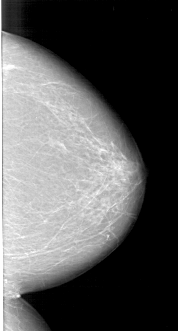

A_1501_1.LEFT_MLO

A_1501_1.LEFT_CC

LEFT_CC LINES 5956 PIXELS_PER_LINE 3106 BITS_PER_PIXEL 12 RESOLUTION 43.5 NON_OVERLAY

LEFT_MLO LINES 6706 PIXELS_PER_LINE 3496 BITS_PER_PIXEL 12 RESOLUTION 43.5 NON_OVERLAY